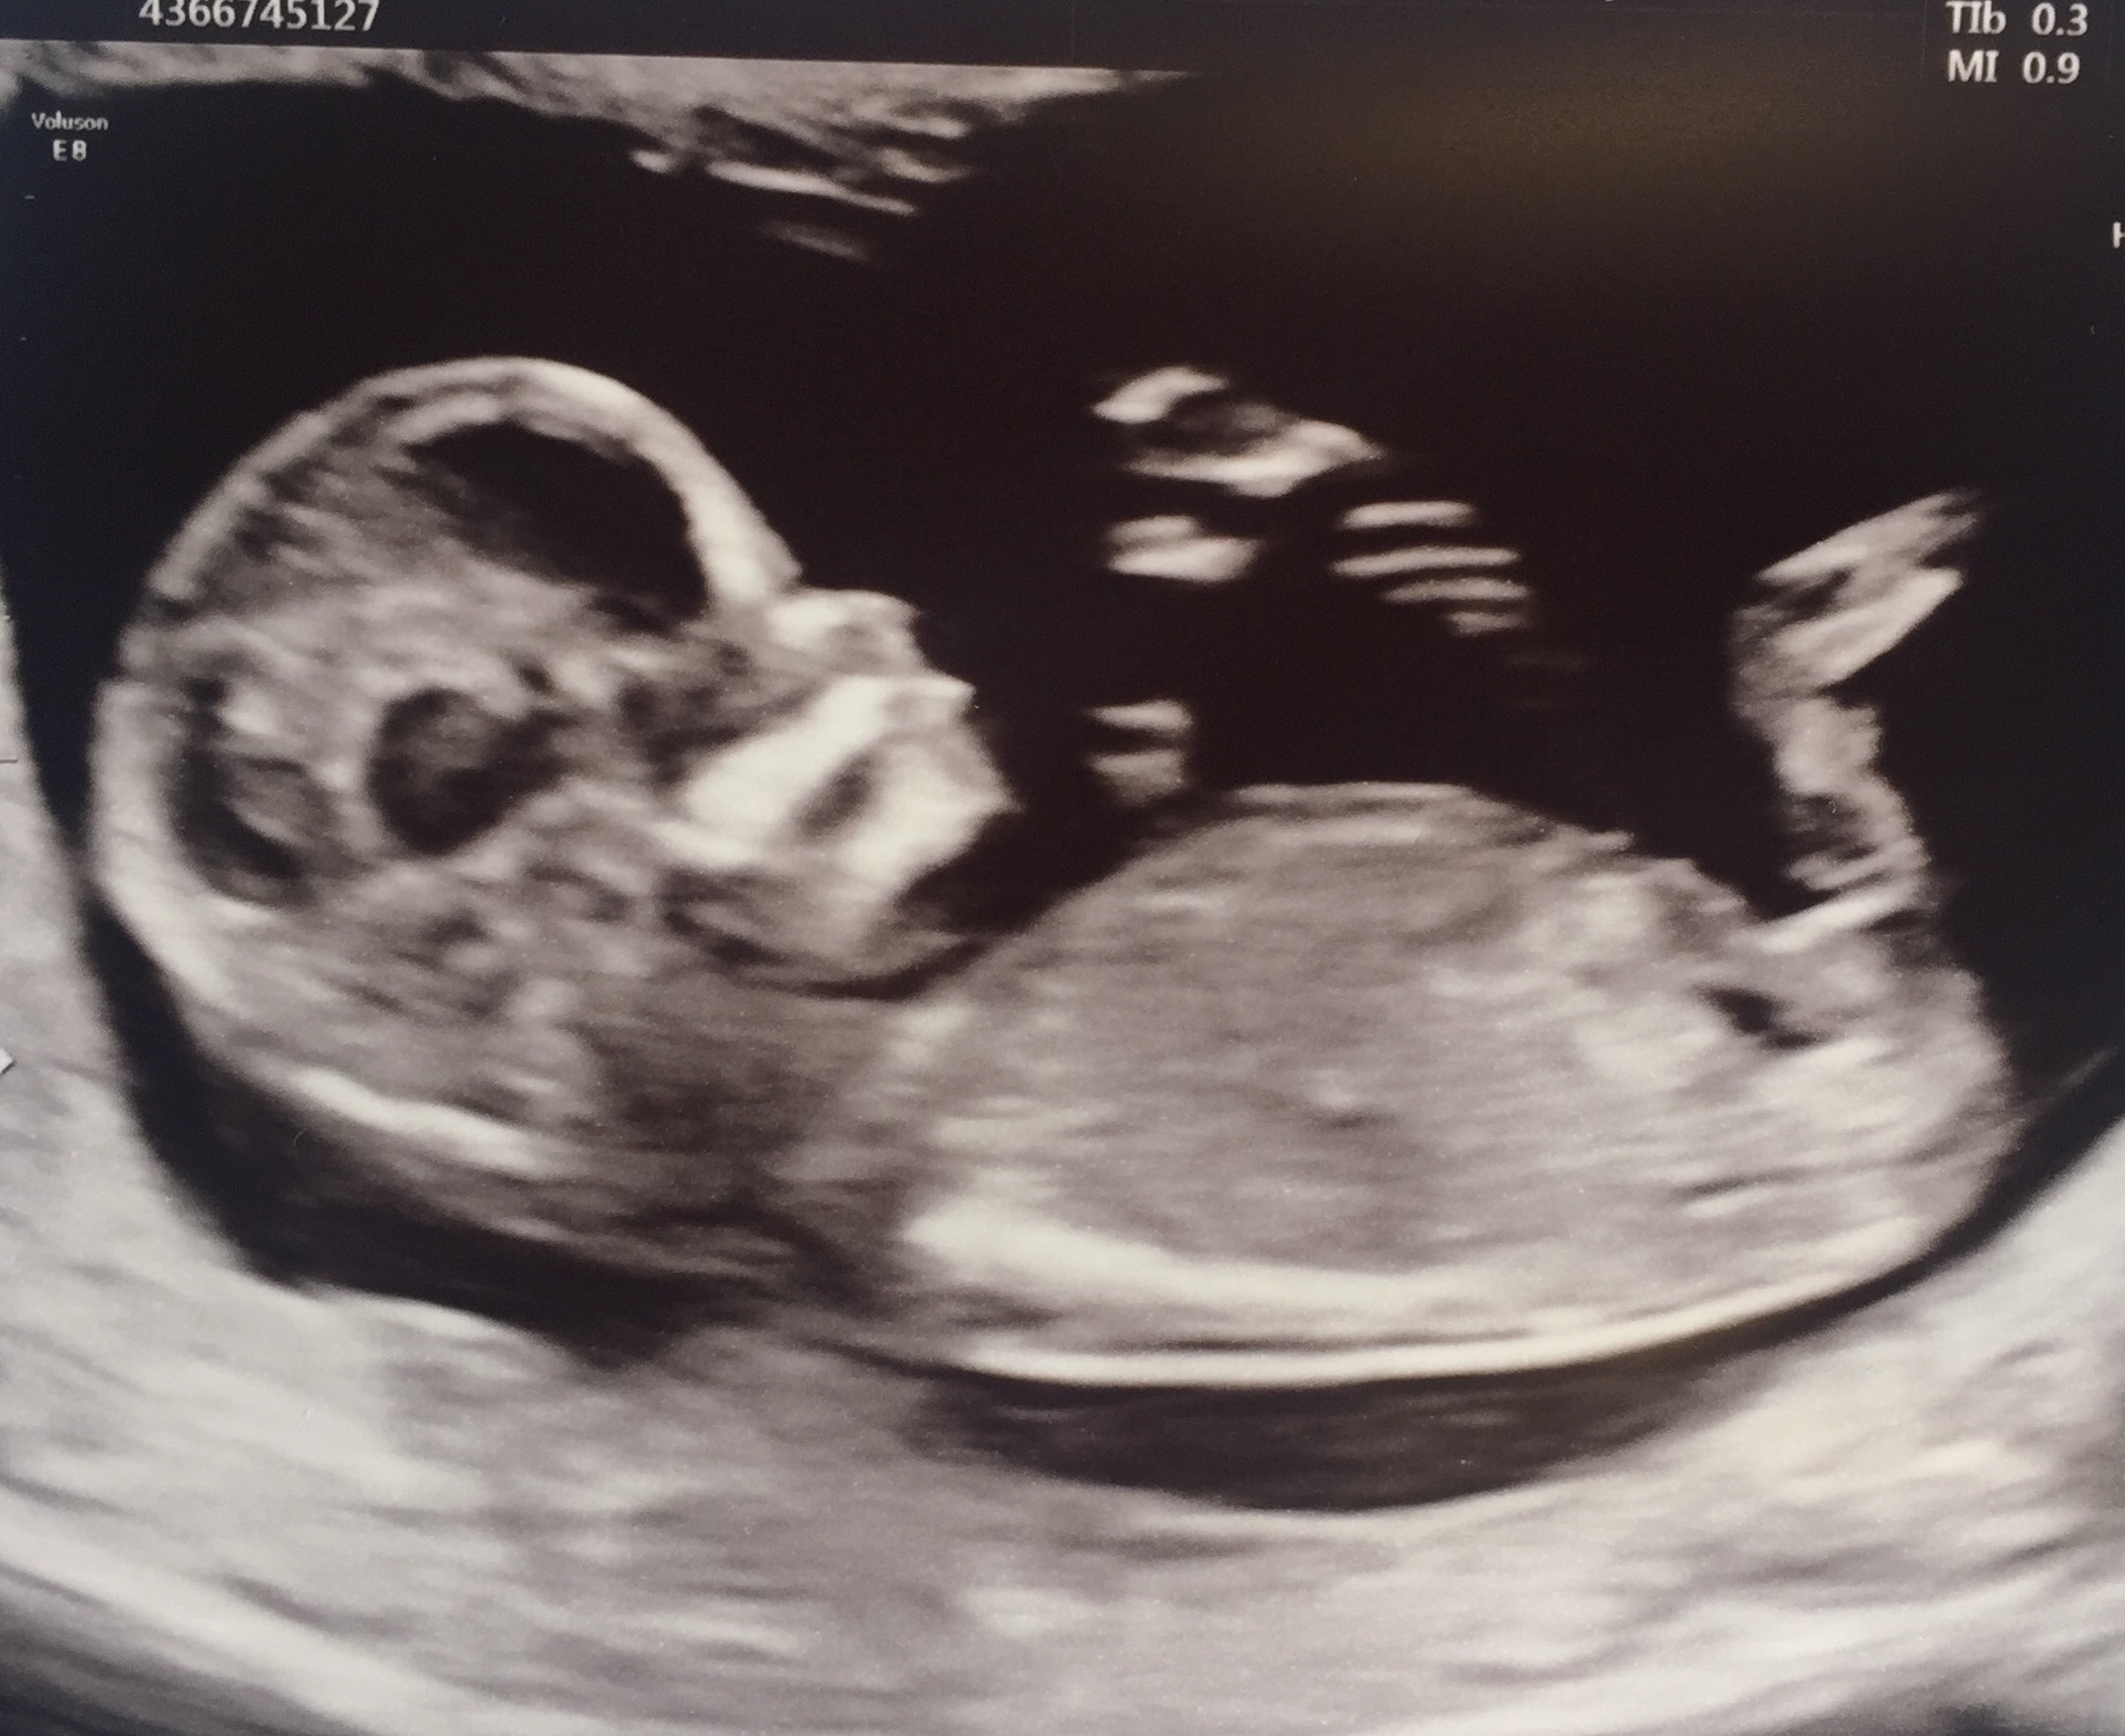

Hi ladies, 12+3 scan pics! Any help and guesses greatly appreciated! By looking at these photos I'm thinking it looks boyish but then also parallel with spine so maybe hope of a girl! I just don't know! XxAttachment 37858

Maybe boy? I think I see stacking in the second pic. The nub does look parallel with the spine but it's still early so still time for the nub to rise. Update us when you find out!

Second pic is giving me boy feels. Congrats on your little one.